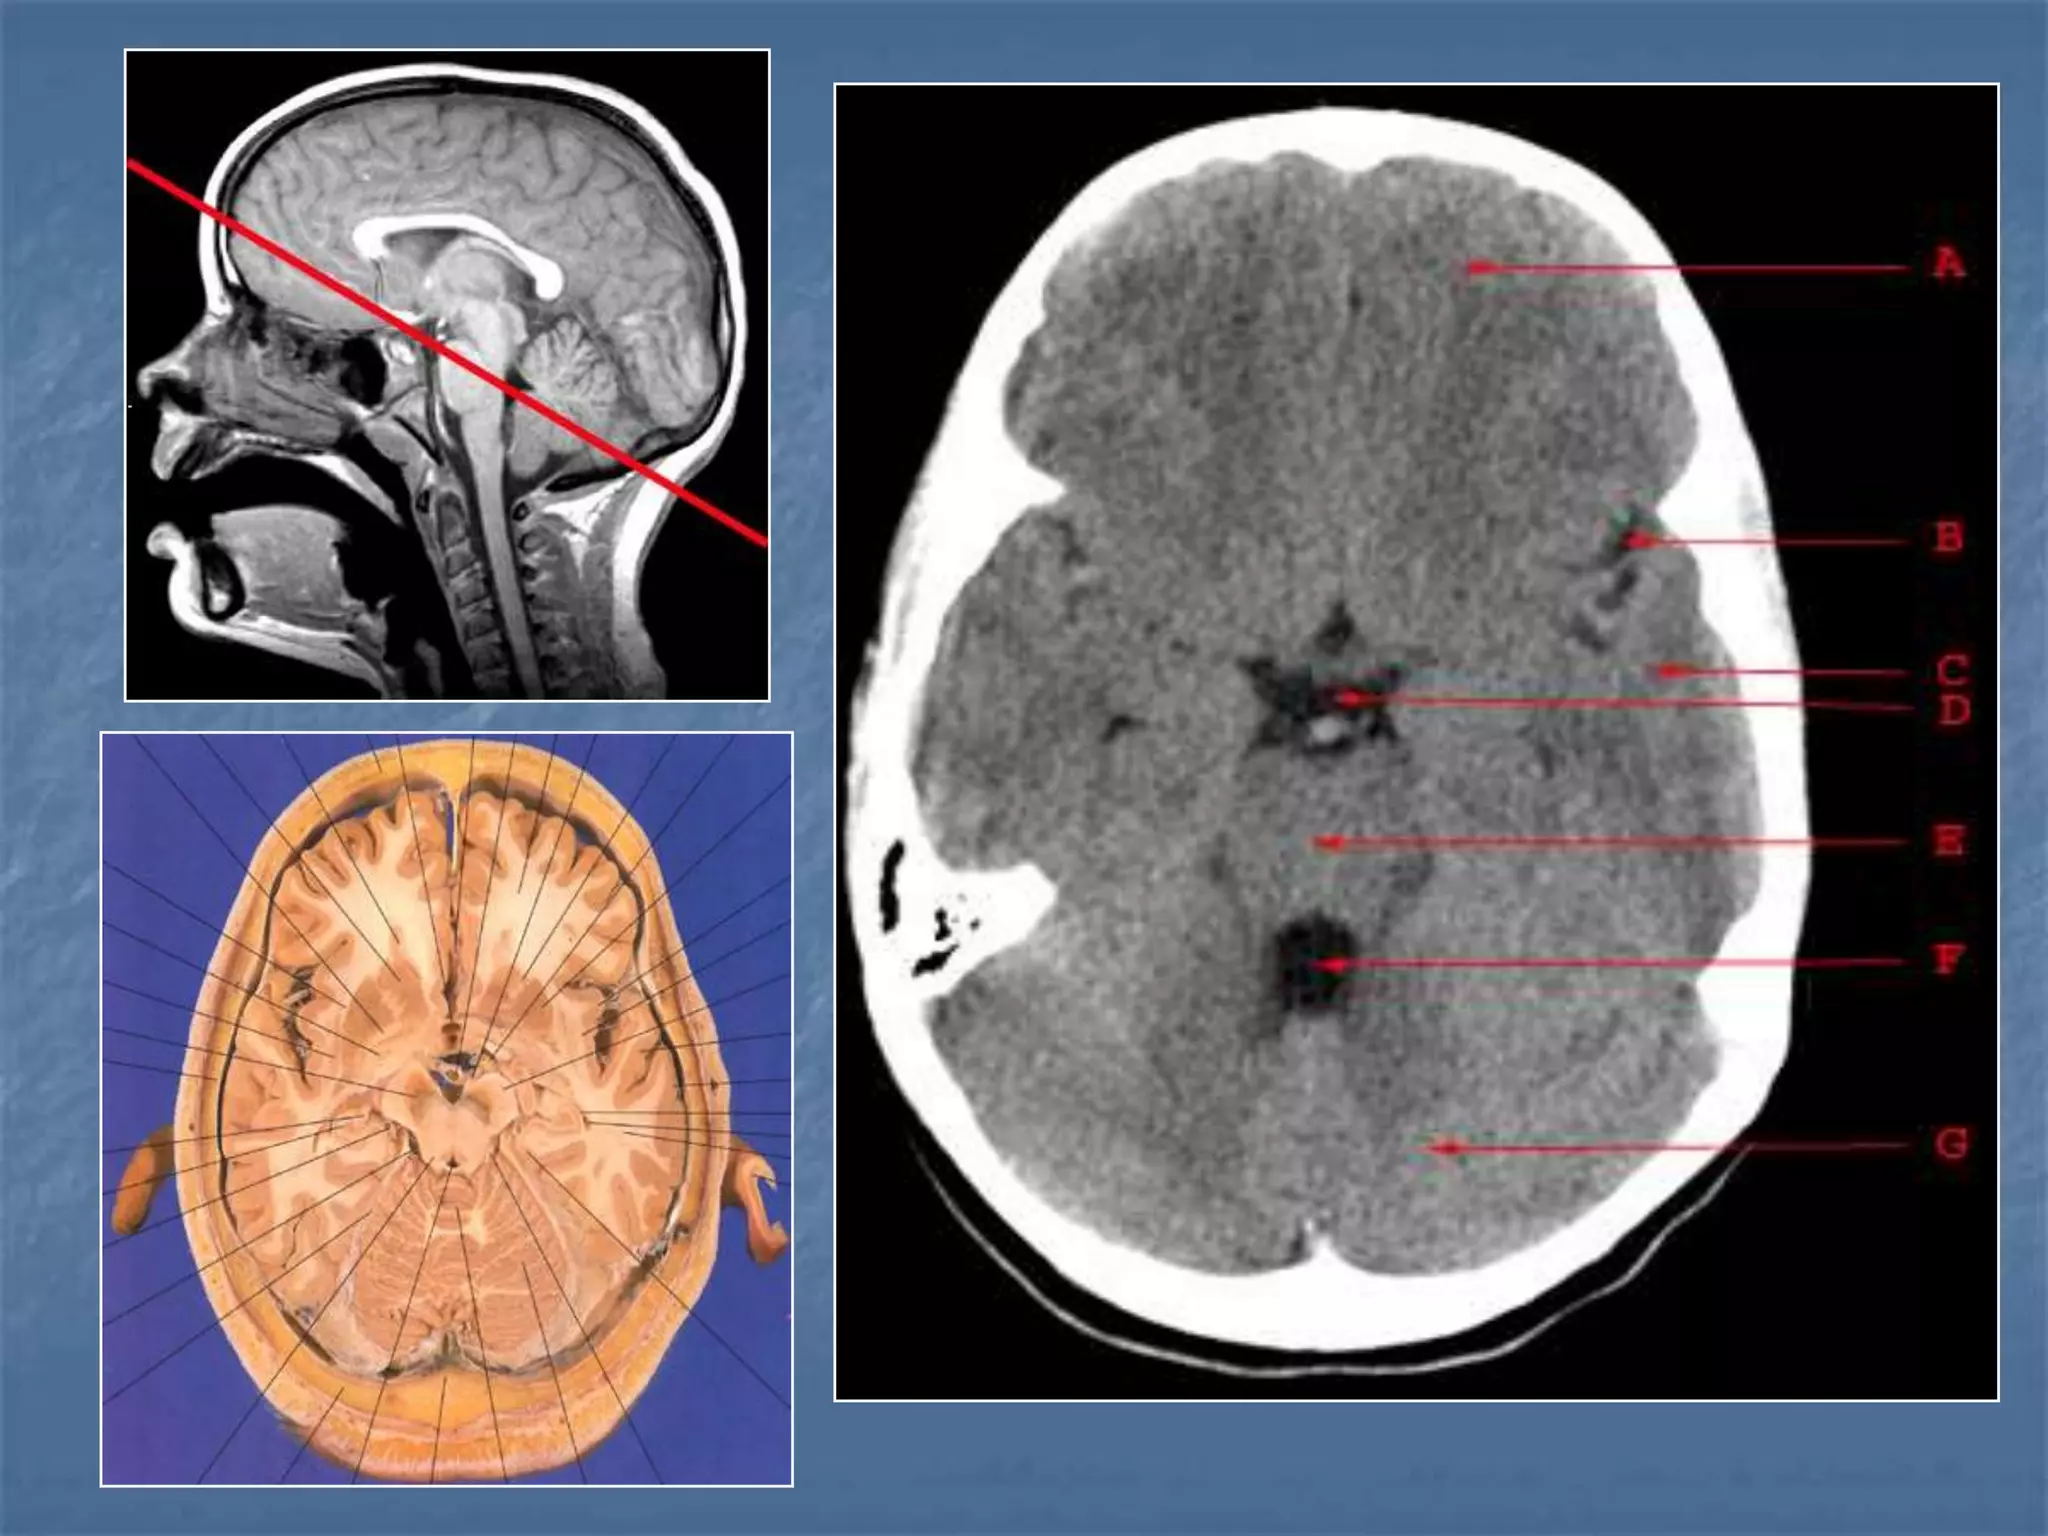

How the CT study is usually planned…

15-20 degree

angulation to

canthomeatal line

to decrease

radiation to the

lens.

 Thinner sections

are studied

through the

posterior fossa

Hounsfield Units

AIR - - 1000

FAT - - 30 to -100

CSF - 0

GREY MATTER - 32 - 41

WHITE MATTER - 23 - 34

ACUTE BLOOD - 56 - 76

CALCIFICATION - 60 - 400

BONE - 1000